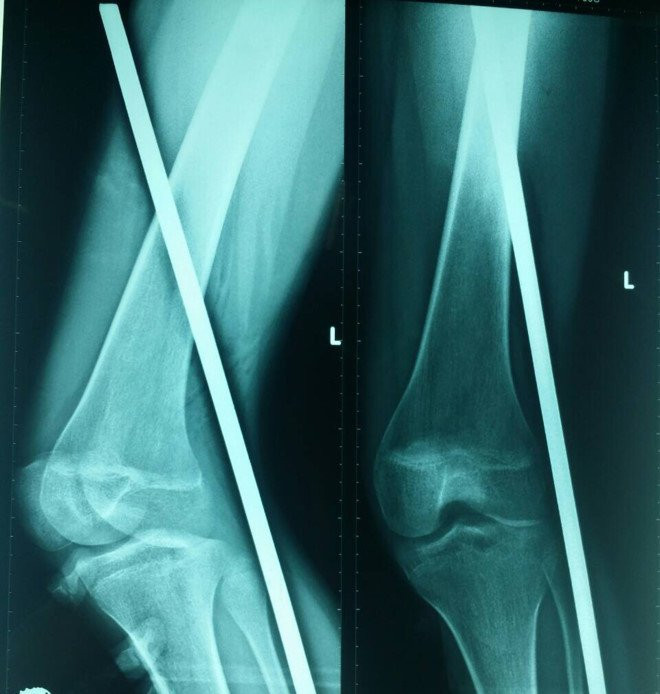

Phim chụp X-quang đoạn sắt đâm xuyên thấu chân bệnh nhân.

Kết quả chụp X-quang cho thấy đoạn sắt đâm xuyên phần mềm không làm tổn thương dây thần kinh, mạch máu.